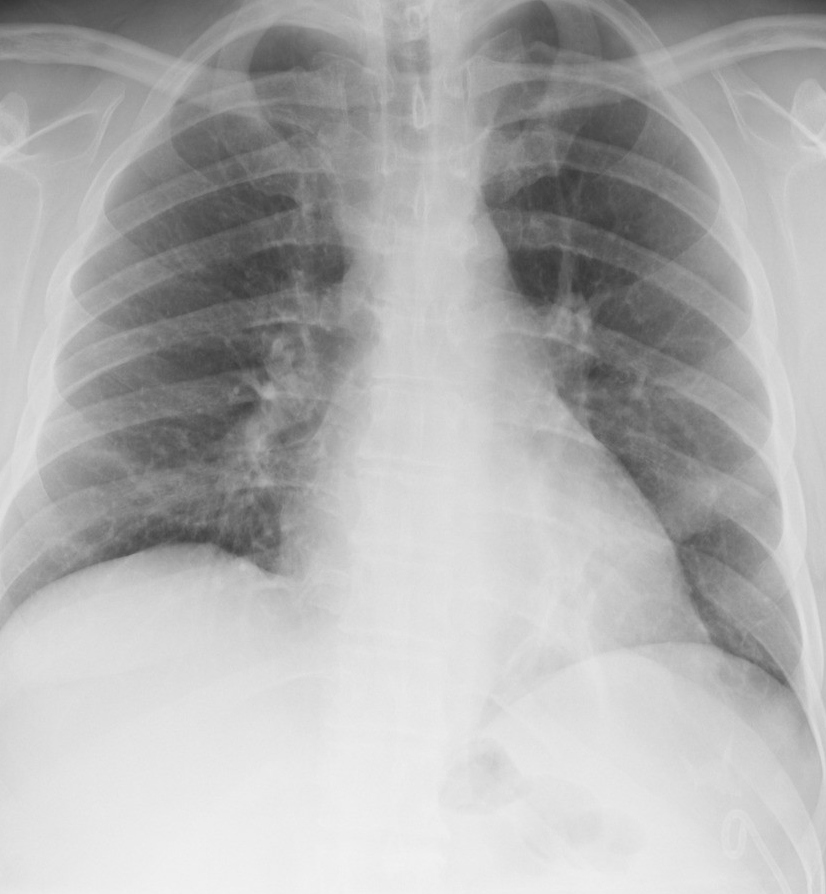

Figure 6 presents image examples for each class retrieved from the RYDLS-20 database. It is worth to mentioning that we have no further information concerning the CXR images with regarding the CXR machine used to take the image, as well as the origin, age and ethnicity of the people whose these images belong to.

Refer to caption

(a) Normal.

(b) COVID-19.

(c) SARS.

(d) MERS.

(e) Pneumocystis.

(f) Streptococcus.

(g) Varicella.

Figure 6: RYDLS-20 image samples.